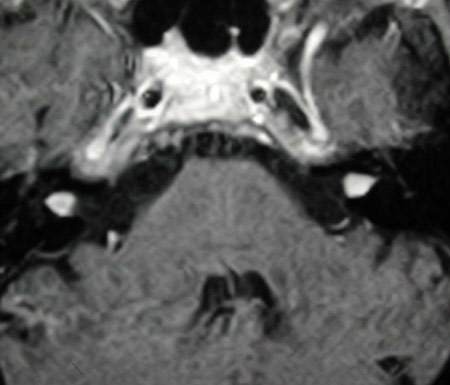

The diagnosis of vestibular schwannoma is made by history, hearing tests, and MRI scan. Gadolinium is a special contrast agent used during the MRI to allow visualization of the tumors. With good technique, MRI will show tumors as small as 2-4 millimeters.

MRI showing bilateral vestibular schwannomas